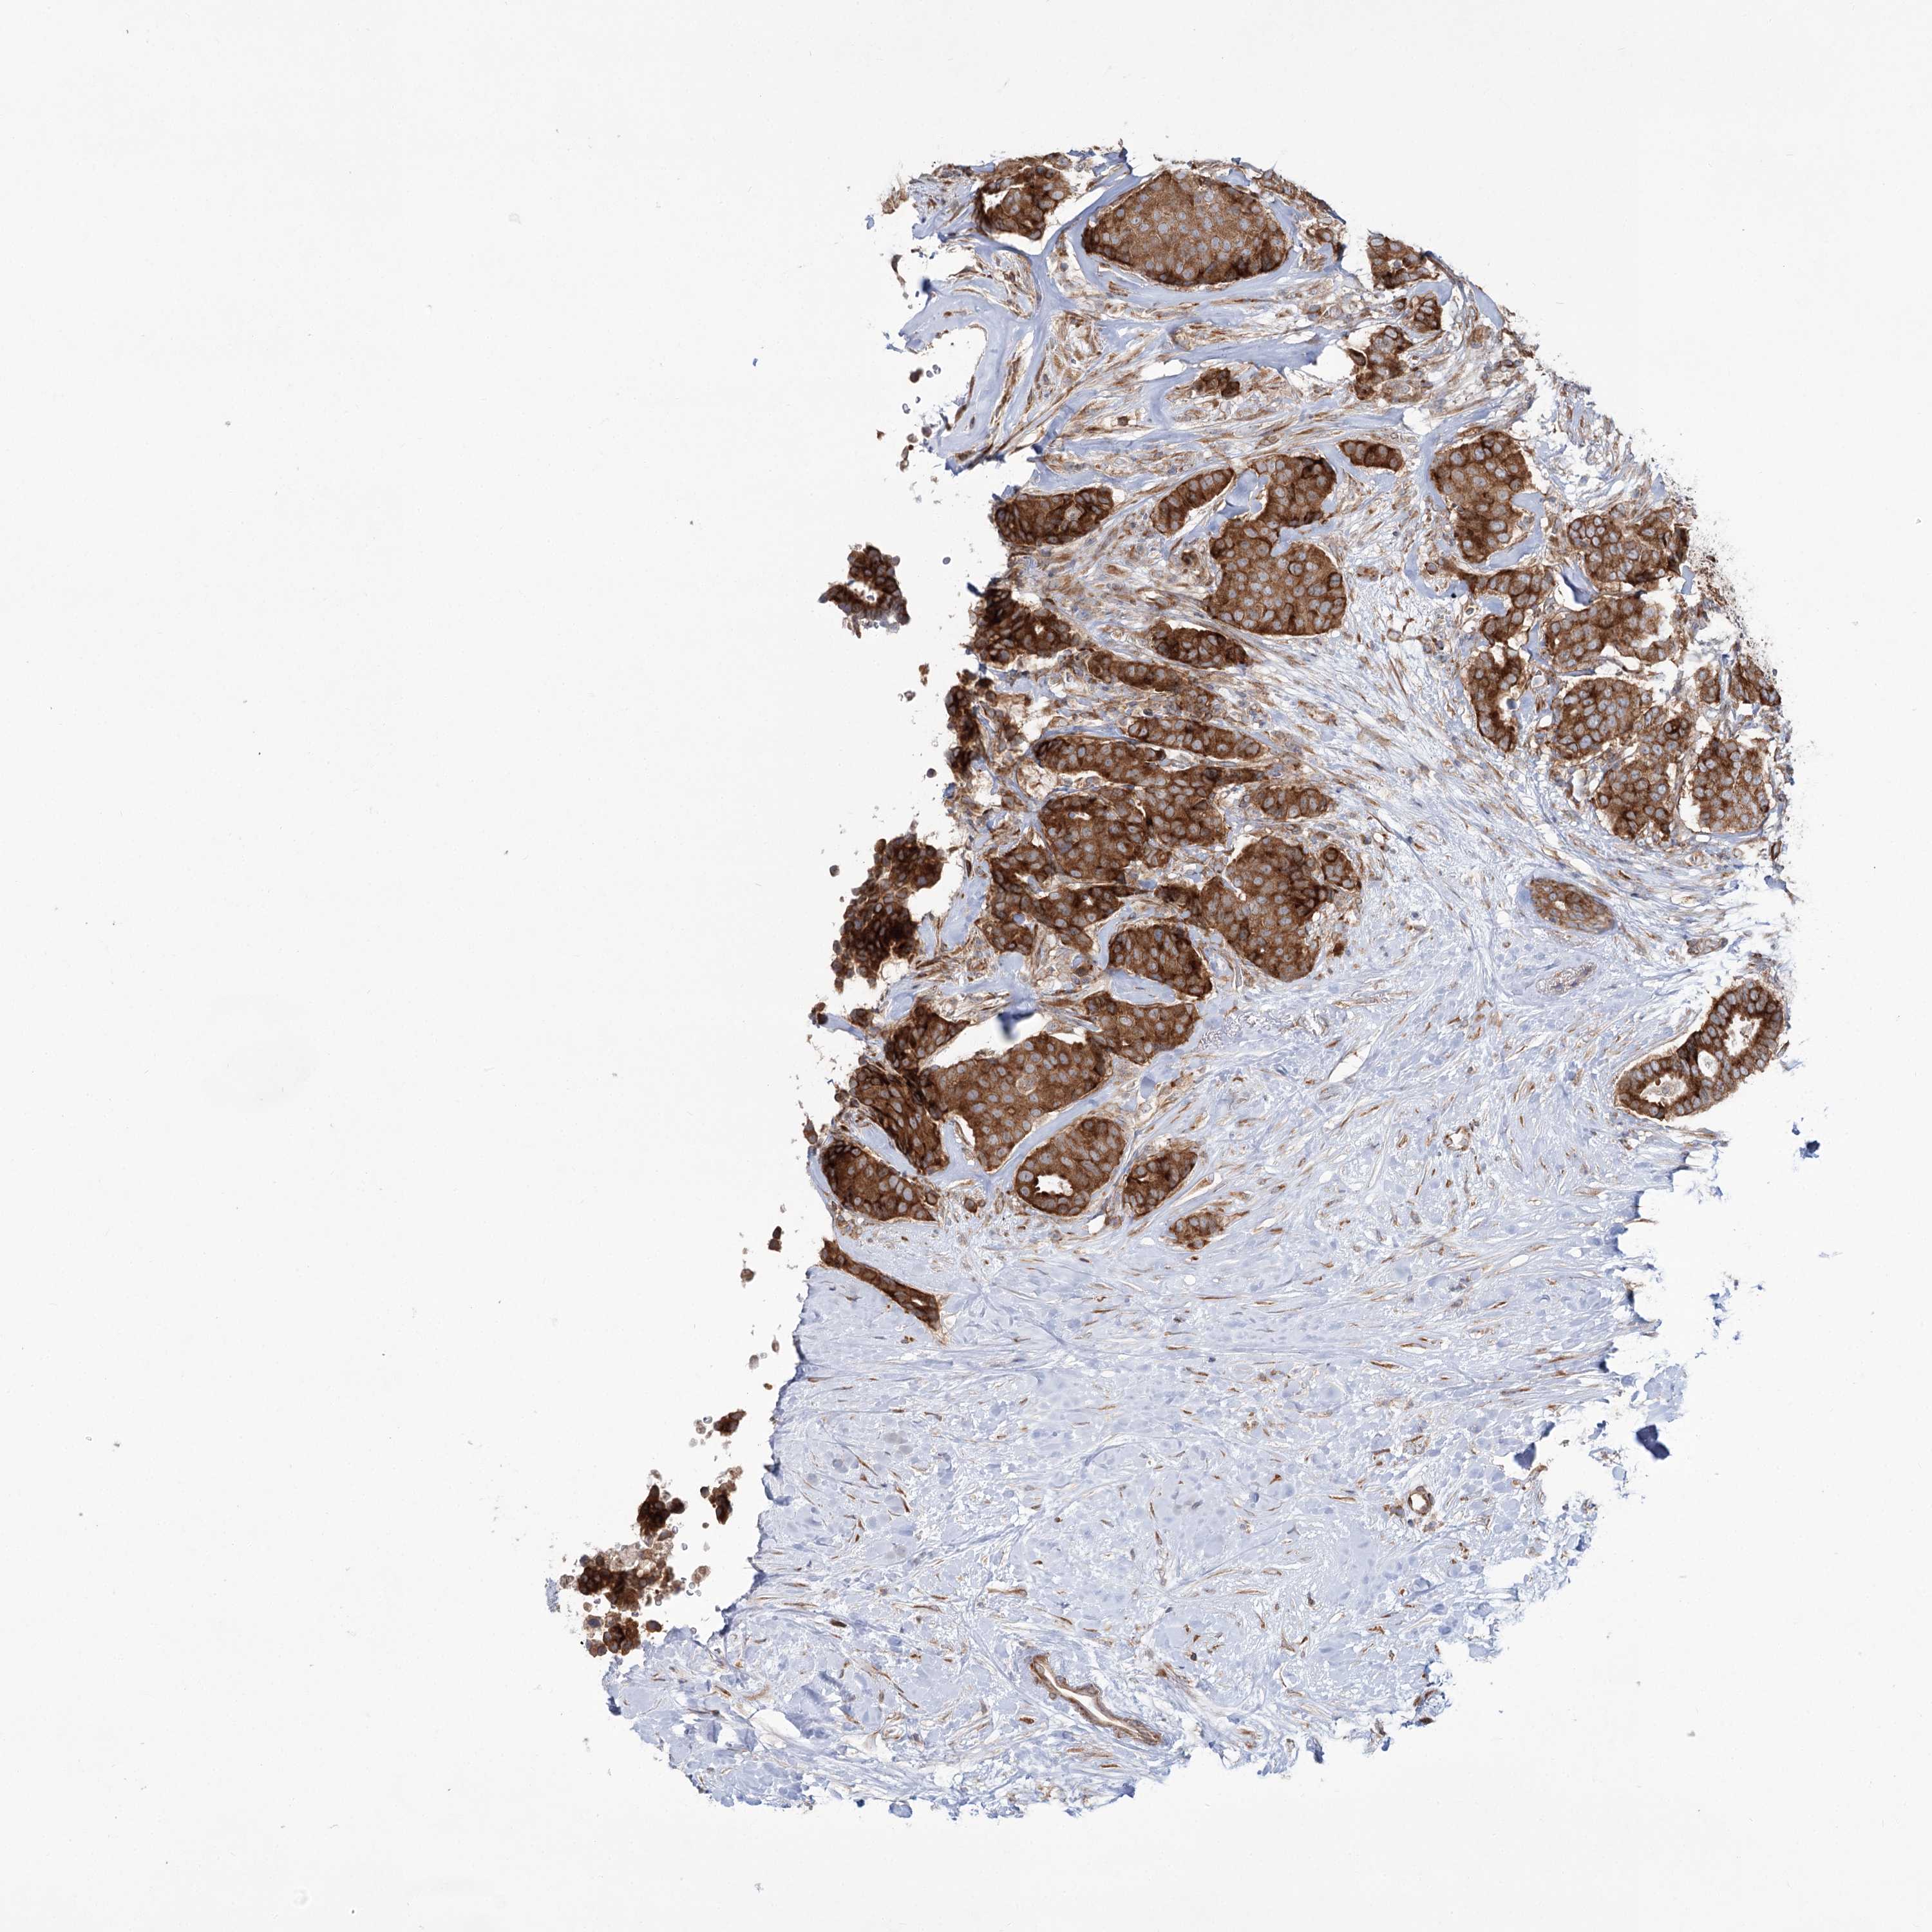

CANCER BREAST CANCER Show tissue menu

BRCA TCGA BRCA VALIDATION PROTEIN EXPRESSION

ANTIBODIES

AND

VALIDATION